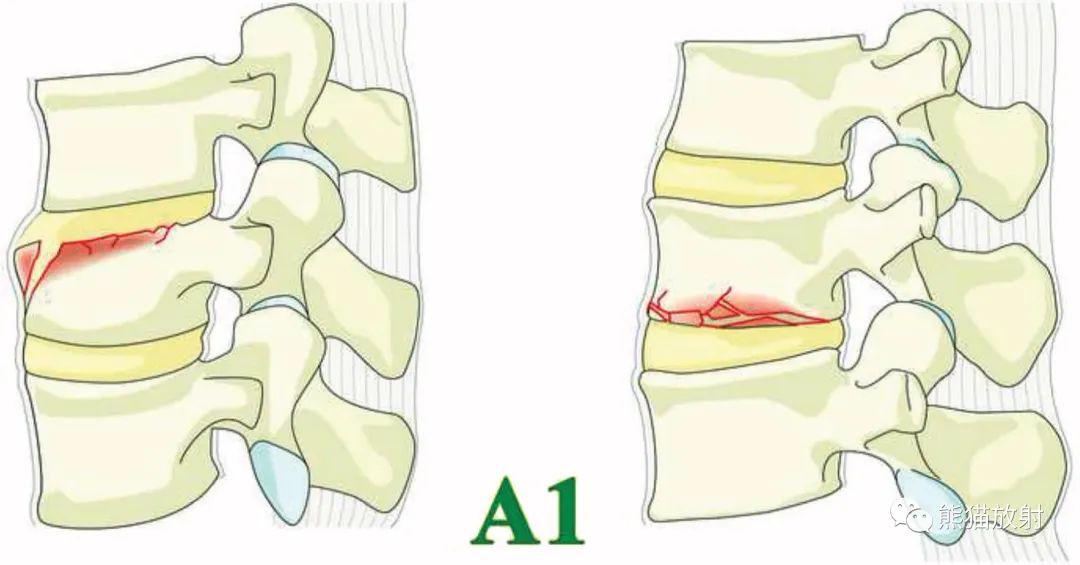

a1亚型-边缘压缩:单一终板骨折未累及椎体后壁.椎管完好无损.图-5.

t3椎体骨折,脊髓损伤